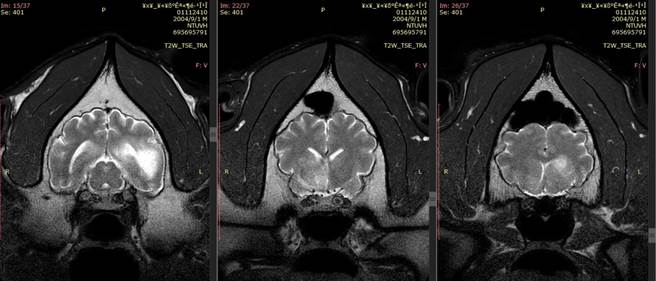

台北立动物园大猫熊「团团」第2次MRI(磁振造影)检查结果出炉,病灶区域明显扩大,病程进展快速,脑部恶性肿瘤的机率大幅提高,然未能进行侵入性切片检查,仍无法百分之百确认。

动物园指出,「团团」第2次MRI影像显示脑部病变除既有的病灶外,区域明显扩大,且出现肿块效应;病程进展快速,推测脑部恶性肿瘤的机率大幅提高,然未能进行侵入性切片检查,仍无法百分之百确认。